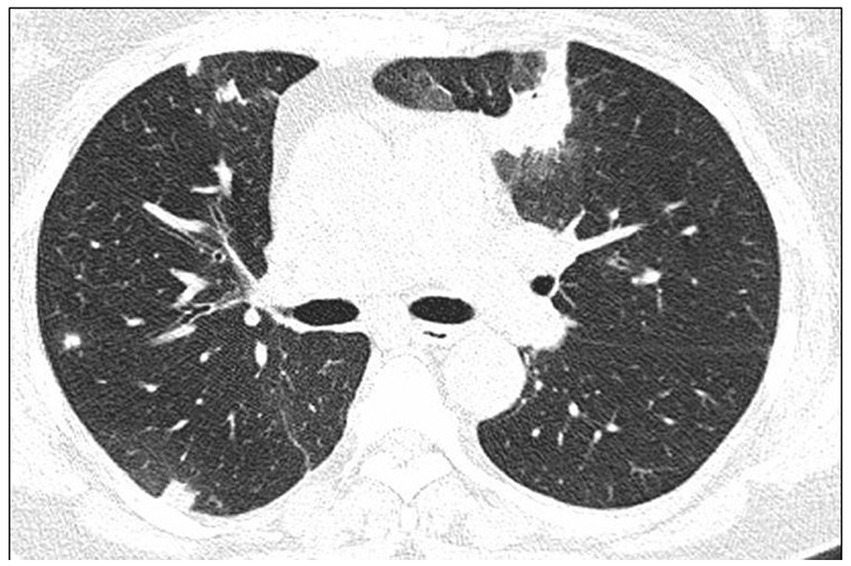

High-resolution computed tomography (HRCT) is the gold standard in the evaluation of OP. It reveals multifocal areas of consolidation, often with a characteristic air bronchogram. Additionally, patchy alveolar consolidations, nodules, areas of ground glass opacity, perilobular infiltrations, bronchial wall thickening, and reticular fibrous changes may be present in peripheral parts of both lungs. Thickening around areas of ground glass opacity with an “atoll” or “crazy-paving” pattern may also be present, although it is less common. Additionally, nodular lesions, pleural thickening, and rarely enlargement of hilar and mediastinal lymph nodes, are present; emphysema or pleural effusion may also be observed (28–40). Honeycomb-type lesions are not in the spectrum of pulmonary changes observed in COP but might be evident in patients who exhibit interstitial pulmonary fibrosis with a component of OP (Figures 2–6).

High resolution computed tomography scan of a patient with COP. Bilateral nodular consolidations.